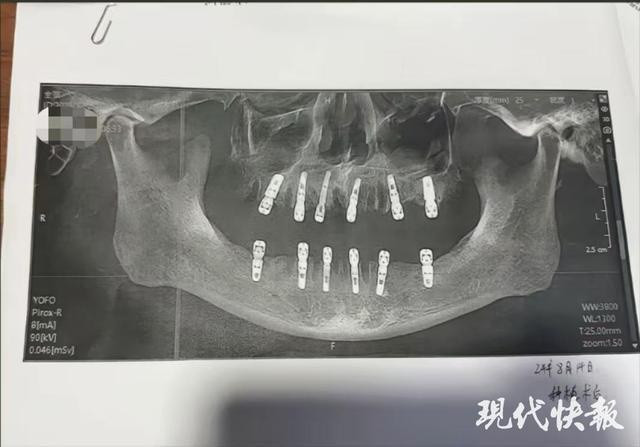

Theo truyền thông Trung Quốc (Bắc Kinh Nhật Báo, ngày 30/7), bà Liu, con gái của nạn nhân cho biết cha mình mắc nhiều bệnh nền như tăng huyết áp, tiểu đường, tim mạch vành và đã đặt 5 stent tim. Dù có hồ sơ sức khỏe đặc biệt, cụ vẫn được chỉ định nhổ 12 chiếc răng và cấy 6 implant trong một lần tại Phòng khám nha khoa Younuo, Cáp Nhĩ Tân vào ngày 17/7. Sau khi rời phòng khám chỉ vài phút, ông bất ngờ nôn ra máu và qua đời ngay sau đó. Đại diện phòng khám xác nhận sự việc và cho biết đã đình chỉ hai bác sĩ trực tiếp phẫu thuật. Sở Y tế thành phố Cáp Nhĩ Tân cũng đã vào cuộc điều tra nguyên nhân.

Cụ ông 77 tuổi tử vong sau khi cấy 6 implant và nhổ 12 răng Ảnh 2